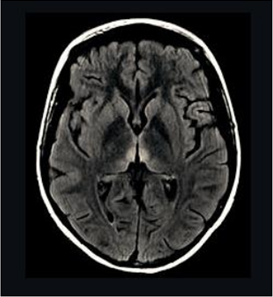

Mulher de 22 anos chega ao pronto atendimento com história de dificuldade para caminhar por falta de equilíbrio há três meses. Evoluiu com piora gradual e hoje deambula somente com apoio. O marido relatou que a paciente realizava atividade física por várias horas diariamente, abandonando a prática devido ao quadro clínico, e que fazia dieta constantemente. Ao exame clínico: paciente muito emagrecida, IMC 16, taquicárdica, sonolenta, com ataxia de marcha, desorientada no tempo e no espaço e com alteração na motilidade ocular extrínseca. A paciente foi internada para investigação. Dois dias após, apresentou piora e foi transferida para a UTI, em coma. A imagem da ressonância magnética de crânio evidenciou a alteração exemplificada pela imagem ao lado e o exame de liquor foi normal. Em relação ao caso apresentado, é correto afirmar:

Provas